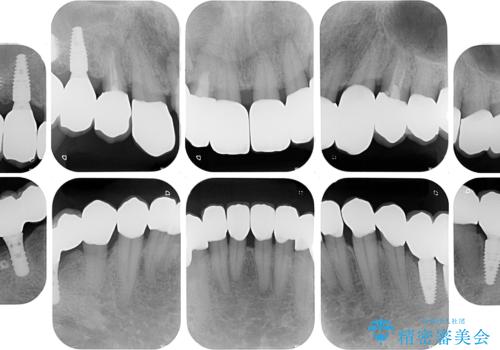

- 奥歯が咬みにくく、前歯がぐらぐらするとのことで来院された患者様です。

咬合力が強く、奥歯が欠損している状態でした。

欠損部はインプラントによる補綴治療を行うこととし、臼歯部が安定した後に、上下前歯部をオールセラミッククラウンにて補綴治療を行うこととしました。